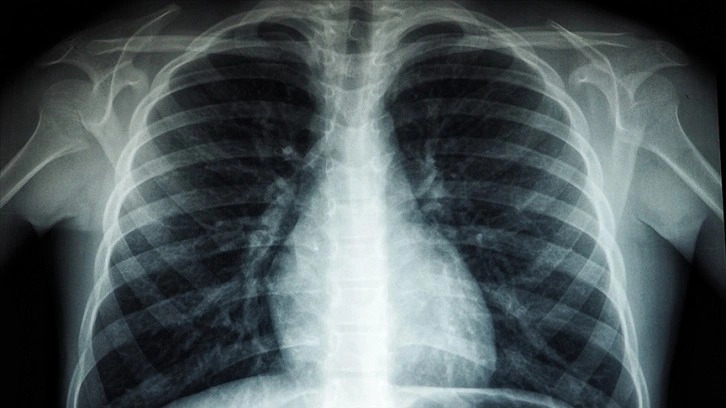

Araştırmacılar, ağır Kovid-19 hastalarında akciğerlerde kan pıhtıları oluşması nedeniyle, Heparin’in kan sulandırıcı etkisinin bu tür pıhtıların oluşumunu engelleyebileceğini aktardı.